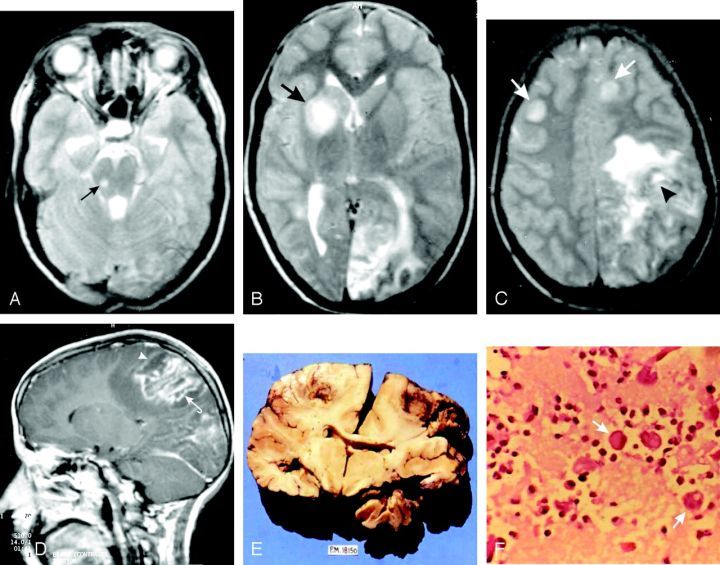

一位19岁的女性患者的大脑影像 , 头痛6个月 , 呕吐1个月 , 步态不稳15天(GAE) , 箭头为病灶 。 非增强CT (A)和增强CT (B)的对比 , 在非增强CT扫描上显示多个椭圆形病灶(箭头) , 提示出血 。 这些病灶在CT增强显示强烈强化(箭头) 。 Amebic Meningoencephalitis: Spectrum of Imaging FindingsP.

感染后会从一个点开始繁殖扩散开来 , 所以你看到病灶都是球形的 。 有些时候只发炎 , 有时候还有出血 , 有些时候就坏掉了……

福氏耐格里所致阿米巴脑膜脑炎的组织病理学研究 。 荧光抗体染色 。